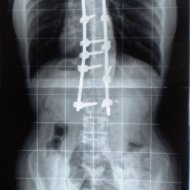

Farklı tipte skolyozu olan hastaların ameliyat öncesi ve sonrası fotoları: